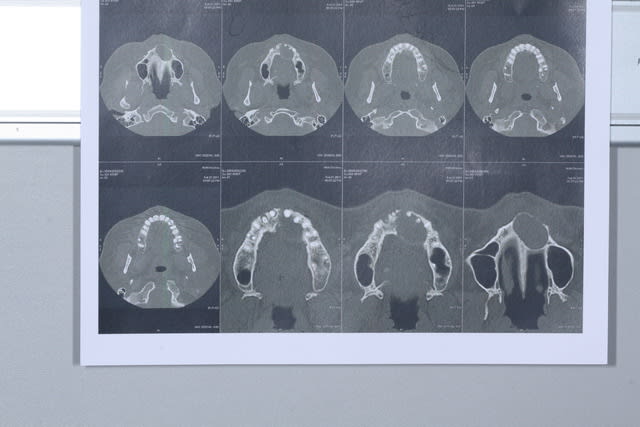

Ce matin j'ai opéré une patiente pour un bon kyste maxillaire d'origine dentaire très certainement et quelques petits sur d'autres dents.

Dans un premier temps j'ai disséqué le kyste qui a détruit le plancher des fosses nasales et le mur palatin.

Dans un second temps j'ai fait des préparations à rétro sur les dents causales (11-21-22-14). Puis j'ai réalisé un collage à rétro car les tenons atteignaient les apex.